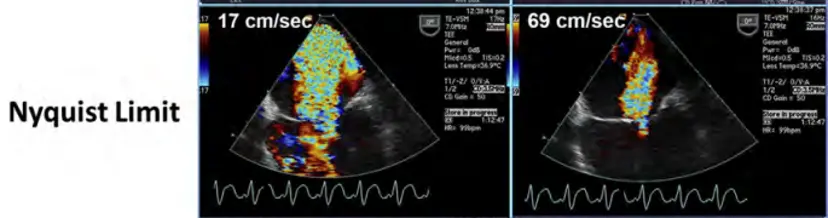

- 🤔 How does the Nyquist limit affect color Doppler visualization of regurgitant velocities?

- A low Nyquist limit will emphasize lower velocities, and thus the jet will be larger.

- ASE Guidelines recommend setting your Nyquist between 50 and 70 cm/sec